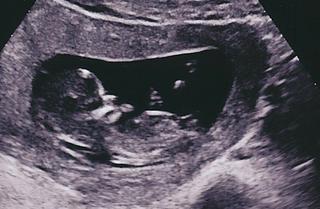

Dievčatá pozrite môj album...Všetko je OK🙂))))))))) krásne to bolo...